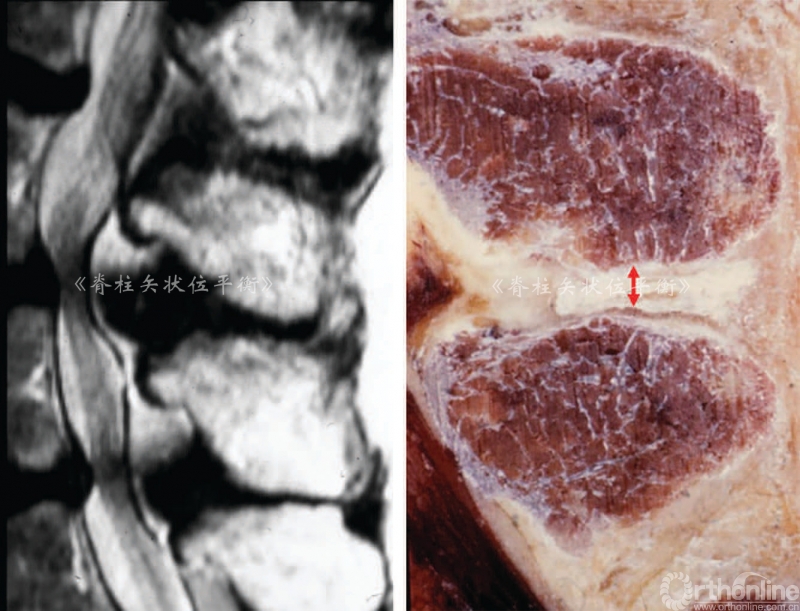

肌肉脂肪化是从深部向表面发展,多裂肌是第一个受累的肌肉,从远端向近端进展(从腰骶部到胸腰部Cruz[3]认为老龄化、腰椎前凸角度丢失和椎旁肌脂肪化程度三者之间呈正相关。

Fortin等[4]对多裂肌的磁共振成像进行了15年以上纵向研究,发现L5~S1多裂肌的萎缩程度显著高于L1~L2。肌肉脂肪化与体力活动(工作和运动)无关,但是与BMI具有相关性。

这种现象在退变性后凸的患者中尤为明显:我们发现在腰椎和胸腰段的受累肌肉严重的纤维化和脂肪化时,2型肌肉纤维几乎完全消失,可以见到虫蚀状、团块状、锯齿状红纤维组织。所有这些组织病理学的征象都可以在肌病中观察到[5](图5)。退变过程累及椎间盘、小关节、韧带和肌肉,导致了腰椎前凸角进行性的丢失。

图5 虫蚀样变(A)、团块样纤维(B)和锯齿样红纤维(C)